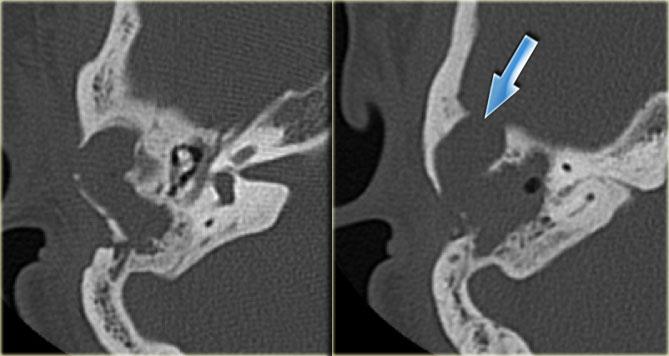

Bên trái là hình ảnh cắt ngang và cắt vành của một bệnh nhân nam 64 tuổi.

Hành tĩnh mạch cảnh nhô lên cao hơn bờ dưới của ống bán khuyên sau (mũi tên).

Hành tĩnh mạch cảnh thường không đối xứng, với hành tĩnh mạch cảnh bên phải thường lớn hơn bên trái.

Khi hành tĩnh mạch cảnh vượt lên trên ống bán khuyên sau, được gọi là hành tĩnh mạch cảnh cao.

Khi vách xương ngăn cách giữa hành tĩnh mạch cảnh và hòm nhĩ bị khuyết, được gọi là hành tĩnh mạch cảnh hở.

Hiếm gặp hơn là hình ảnh túi phình nhỏ – được gọi là túi thừa hành tĩnh mạch cảnh.

Bên trái là hình ảnh cắt ngang và cắt vành của một bệnh nhân nam 50 tuổi.

Phát hiện tình cờ túi thừa hành tĩnh mạch cảnh (mũi tên).